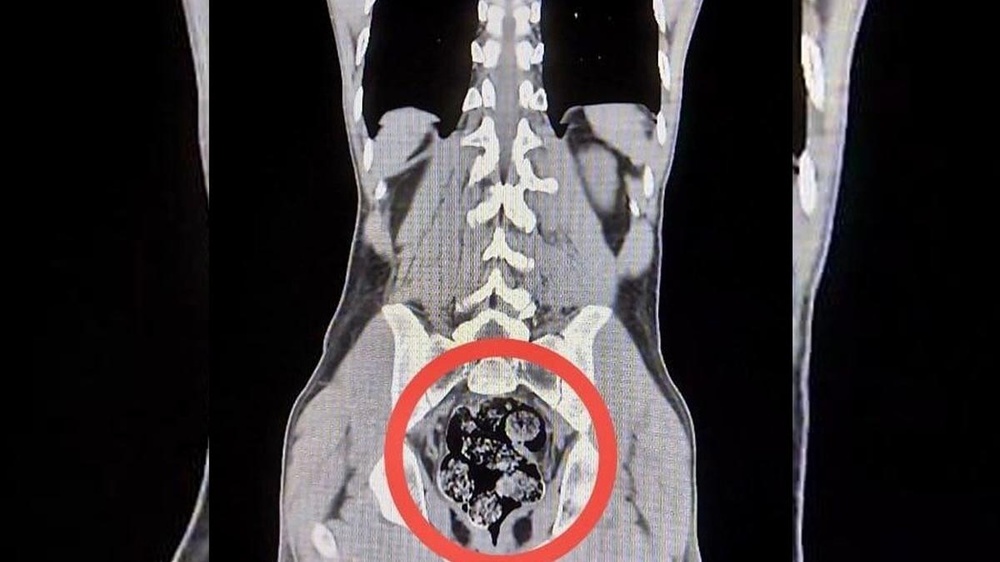

در بازرسی اولیه از وسایل و لباسهای این افراد، هیچ ماده مخدری کشف نشد. با این حال، به دلیل مشکوک بودن وضعیت جسمانی یکی از متهمان، هر دو به بیمارستان دولتی حارکانی منتقل شدند. بررسیهای پزشکی نشان داد که امیر رافعی. س. در معده و رودههای خود ۷ بسته حاوی ۲۰۳/۰۲ گرم ماده مخدر صنعتی متامفتامین (کریستال) جاساز کرده است.

این بستهها با انجام عمل جراحی از بدن متهم خارج شد. در ادامه، هر دو مظنون به دادگاه معرفی شدند و پس از تکمیل مراحل قضایی، به اتهام «تولید و قاچاق مواد مخدر یا محرک» بازداشت و به زندان منتقل شدند.